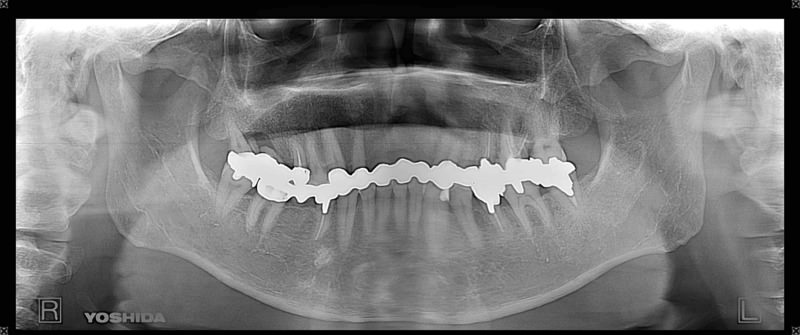

症例140代 男性 主訴 奥歯に歯を入れたい、しっかり噛みたい

治療前

治療後(5年経過)

主訴 奥歯がない為、食事が不自由である。入れ歯は煩わしいので、固定制のインプラントにして欲しいと訴え来院。口腔内全体で6本のインプラントを埋入。仮歯にて神経筋機構、顎関節のバランスを整え、リハビリを経て、約5ヶ月後にジルコニアを装着。

リスクとしては、外科的侵襲がある。デメリットは、保険外診療の為、経済的負担がある。

費用 316万(税込) (オペ・仮歯・最終補綴物まで含む)